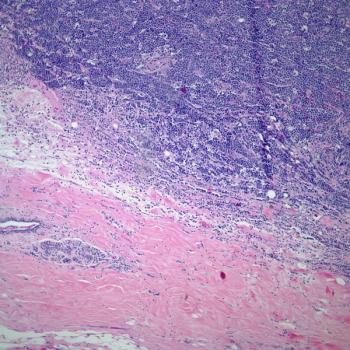

A 35-year-old man presents with severe headaches, and a biopsy is obtained. What is your diagnosis?

A 58-year-old man presents with severe headaches, and a biopsy is obtained. What is your diagnosis?